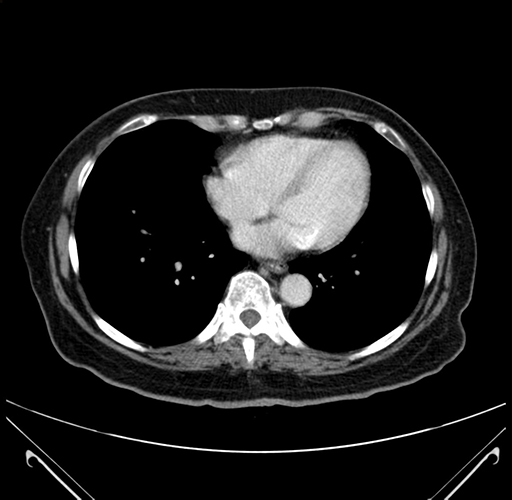

Pre-Chemo: Axial Venous

Axial Venous

Imaging analysis

Based on your CT findings, which issue(s) would give reason for "planned slowing down moment(s)" in this case?

Considering a standard right hepatectomy procedure, what step(s) of the operation would you do differently in this case?